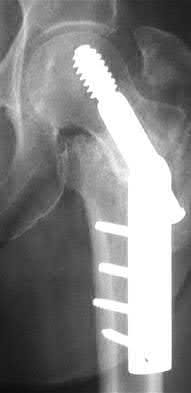

3. # Which of the following is not an appropriate implant for treatment of the fracture seen in Figure A?

5. Sliding hip screw Corrent answer: 5

The image shows a reverse obliquity intertrochanteric hip fracture.

According to the referenced article by Haidukewych et al, unstable peritrochanteric hip fractures have a worse outcome (failed in 9/16 cases) if treated with a sliding hip screw. Two additional factors that were found to have a strong correlation with postoperative failure (nonunion, loss of reduction) were poor reduction and poor implant placement. In this study, fixed angle devices were superior. Intramedullary fixation has the added advantage of a shorter lever arm and less potential for fracture collapse and limb shortening.

The IMN also acts as a medial buttress.

According to Sanders et al, the dynamic condylar screw (DCS) can also be used in subtrochanteric models, but should not be used if extensive comminution is seen, as they reported a high failure rate with DCS in these fractures if highly comminuted. They report a 77% overall union rate with this device.